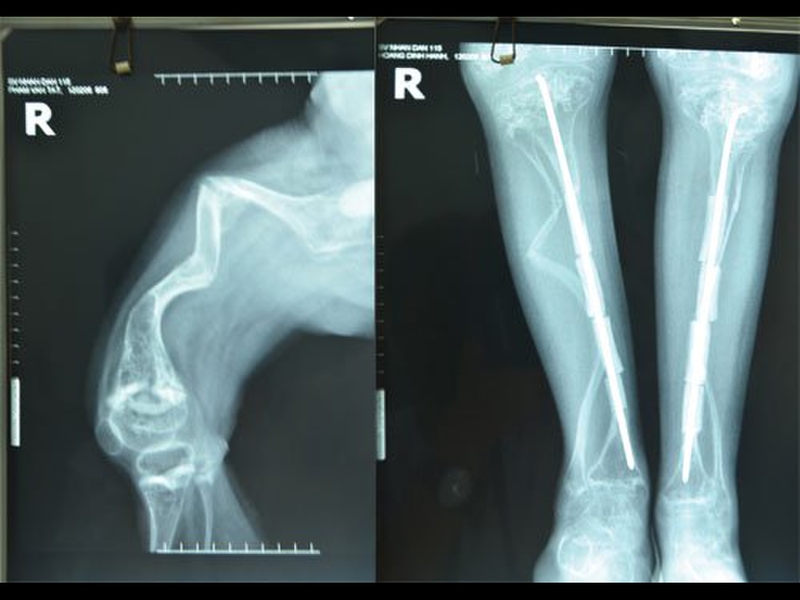

Đây là phương pháp can thiệp từ bên ngoài, hỗ trợ thêm cho khung xương trong việc chống đỡ cơ thể. Bác sĩ sẽ chèn các thanh kim loại vào ống tủy để nâng cao sức chịu đựng của xương, cải thiện cong vẹo cột sống. Hoặc đặt các thanh vào xương dài để làm xương vững chắc, ngăn ngừa và sửa chữa việc tạo xương bất thường. Tuy nhiên, nhược điểm của phương pháp là có thể để lại một số di chứng lên não bộ, thần kinh hoặc tủy sống.